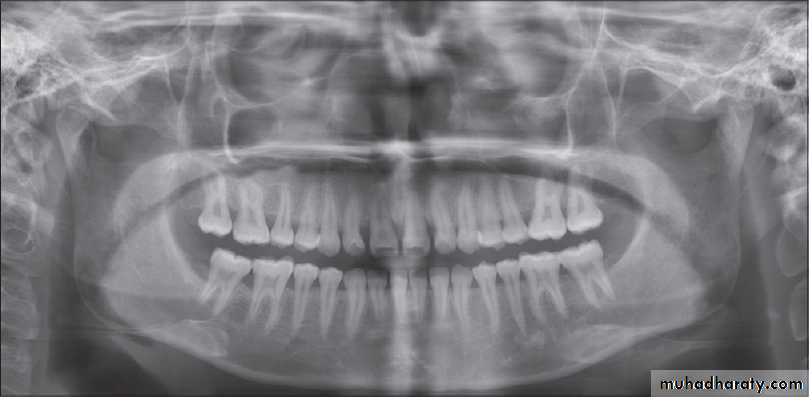

Radiology

it is not specific!

# Radiology demonstrates reduction in bone density in the TMJ.

# Marked erosion of the condylar head and articular fossa.

# Narrowing of the joint space.

In long-standing disease, there is:

• destruction of entire condyle• anterior open bite

• secondary osteoarthrosis

• ankylosis.